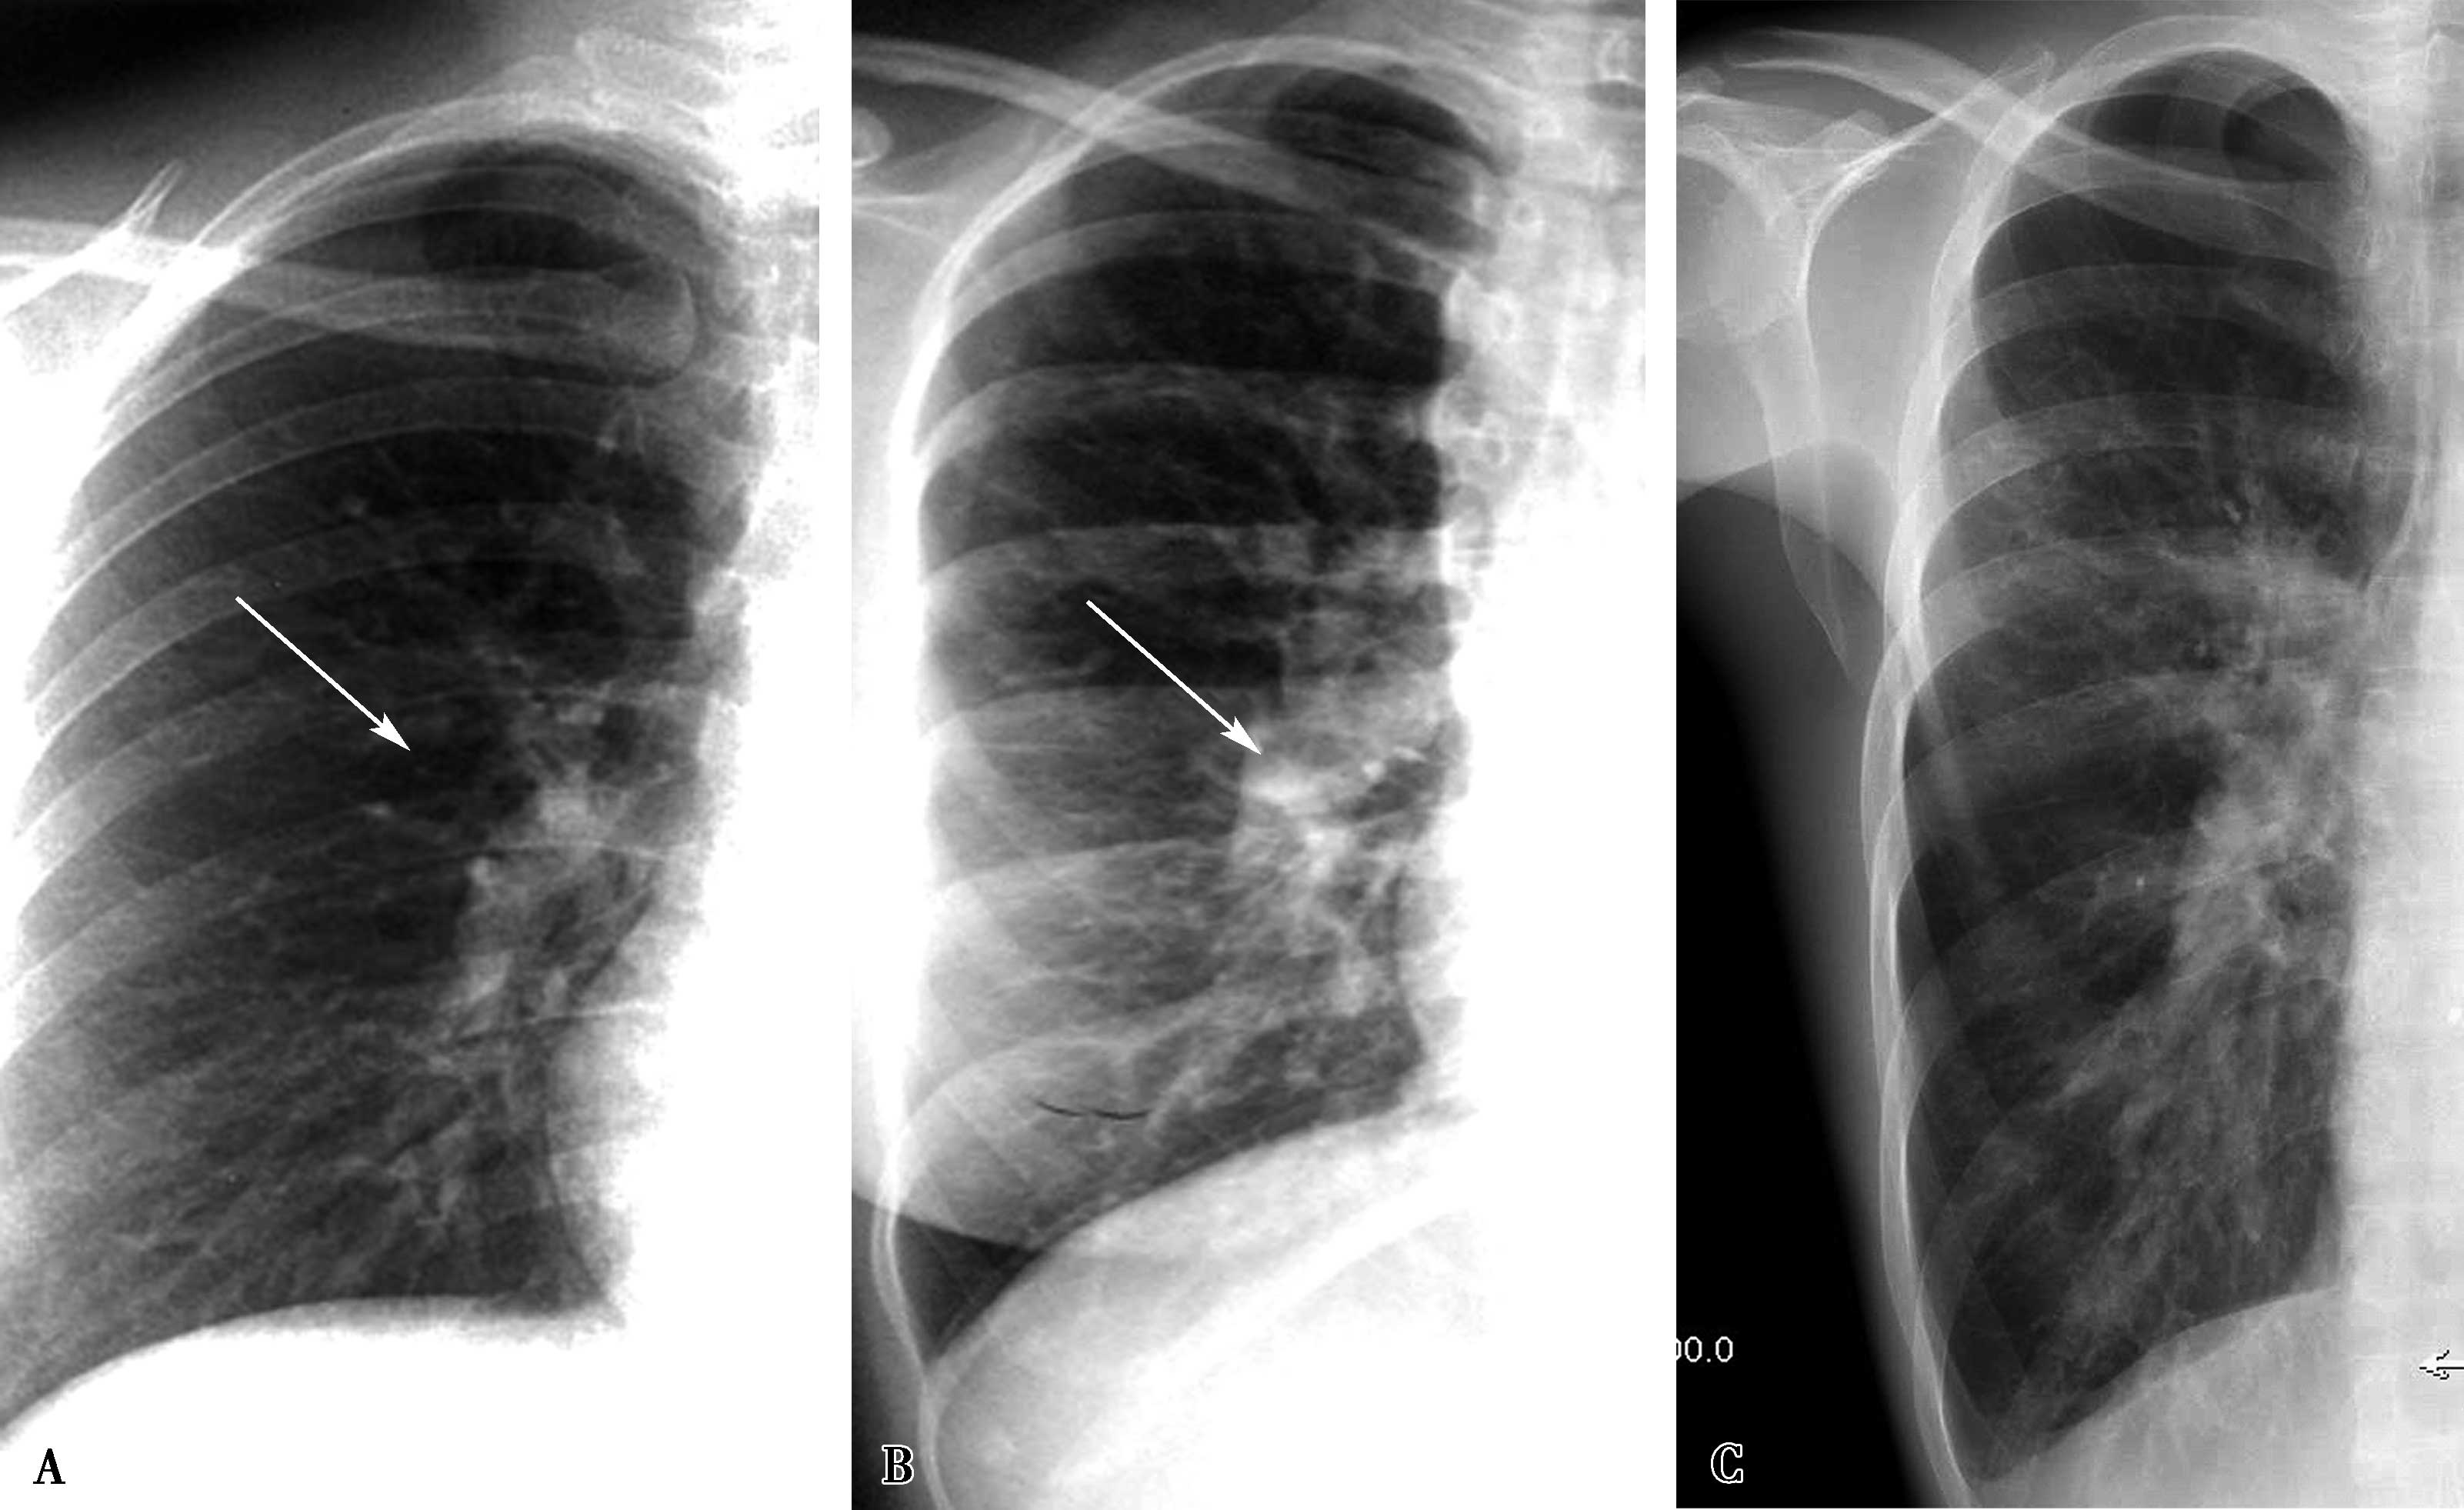

(二)两肺血不均匀减少

X线表现为按一侧肺或按肺叶、肺段分布的肺血减少。见于:①先天性肺动脉畸形,如一侧肺动脉缺如、叶-段局部肺动脉狭窄;②获得性肺血管疾患:各种病因导致局部肺动脉狭窄-梗阻(如血管炎,肺栓塞等);③胸-肺部疾患,如肺气肿、肺大疱等导致局部肺血减少。

1.大动脉炎 “肺动脉型”(图7-2-4)

X线征象:①肺血分布不均匀;②受累血管供血区肺血减少;③正常部分代偿性肺血增多。

图7-2-4 女,37岁,大动脉炎(肺动脉型),右肺动脉重度狭窄。右侧肺血减少

A.心脏远达,右肺血减少,右心室增大;B.CTPA三维重建(VR),示右肺动脉重度狭窄(↑)

2.先天性一侧肺动脉缺如(图7-2-5)

图7-2-5 男,20岁,先天性一侧肺动脉缺如 右侧肺透过度增高,肺血明显减少(▲)。右膈升高(↑),右肺容积减小;右心增大,肺动脉高压

三、肺淤血

(一)两肺淤血

主要见于二尖瓣病变;各种原因引起的左心功能不全(如冠心病、高血压性心脏病、心肌病左心功能不全等);肾功能不全等。根据程度分为肺淤血、间质性肺水肿及肺泡性肺水肿,X线表现见本章第一节(图7-2-6)。

图7-2-6 男,50岁,高血压冠心病,左心功能不全,间质性肺水肿。X线胸片示两肺透过度低,间隔线—Kerley B、C线见于中下肺野外带(▲),叶间胸膜影增厚(↑)

(二)节段性肺淤血(肺水肿)

X线表现为按一侧肺或按肺叶、肺段分布的肺淤血(或肺水肿)。见于:①先天性一侧或叶-段肺静脉闭锁或狭窄;②获得性:心源性肺淤血或肺水肿可以由于肺部基础疾患,可以表现分布不均匀,如肺气肿、肺大疱;获得性局部肺静脉狭窄-闭塞,导致局部肺淤血或肺水肿(图7-2-7)。

部分肺静脉闭塞:见于先天性部分性或获得性部分肺静脉狭窄-闭塞。X线征象:①受累区域可见间隔线;间质性肺水肿;②受累区域可见中心肺泡水肿;③先天性肺静脉闭锁可见相应肺叶实变不张或发育不全(图7-2-8)。

图7-2-7 右肺上叶及中叶肺水肿(间质性及肺泡性肺水肿)

造影证实为右上肺静脉闭塞;A.胸部正位;B.HRCT冠状位重建,可见典型小叶间隔增厚(↑),肺泡性水肿(▲)

图7-2-8 女婴,3个月,气促,发绀;X线胸片示右下肺实变不张(A↑);右心增大。CTA:右下肺静脉闭锁(BC↑),右肺下叶实变不张,右心房室增大。肺动脉高压